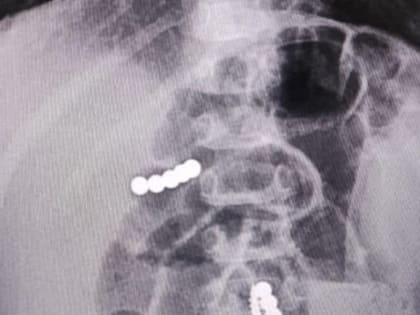

Биоимпланты начали устанавливать пациентам ставропольской краевой больницы

В Ставропольской краевой клинической больнице в практику нейрохирургии внедрили инновационные методы лечения болей в спине.